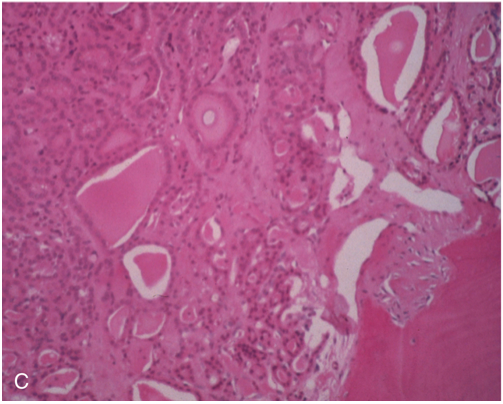

mets that look like this:

A

thyroid cancer